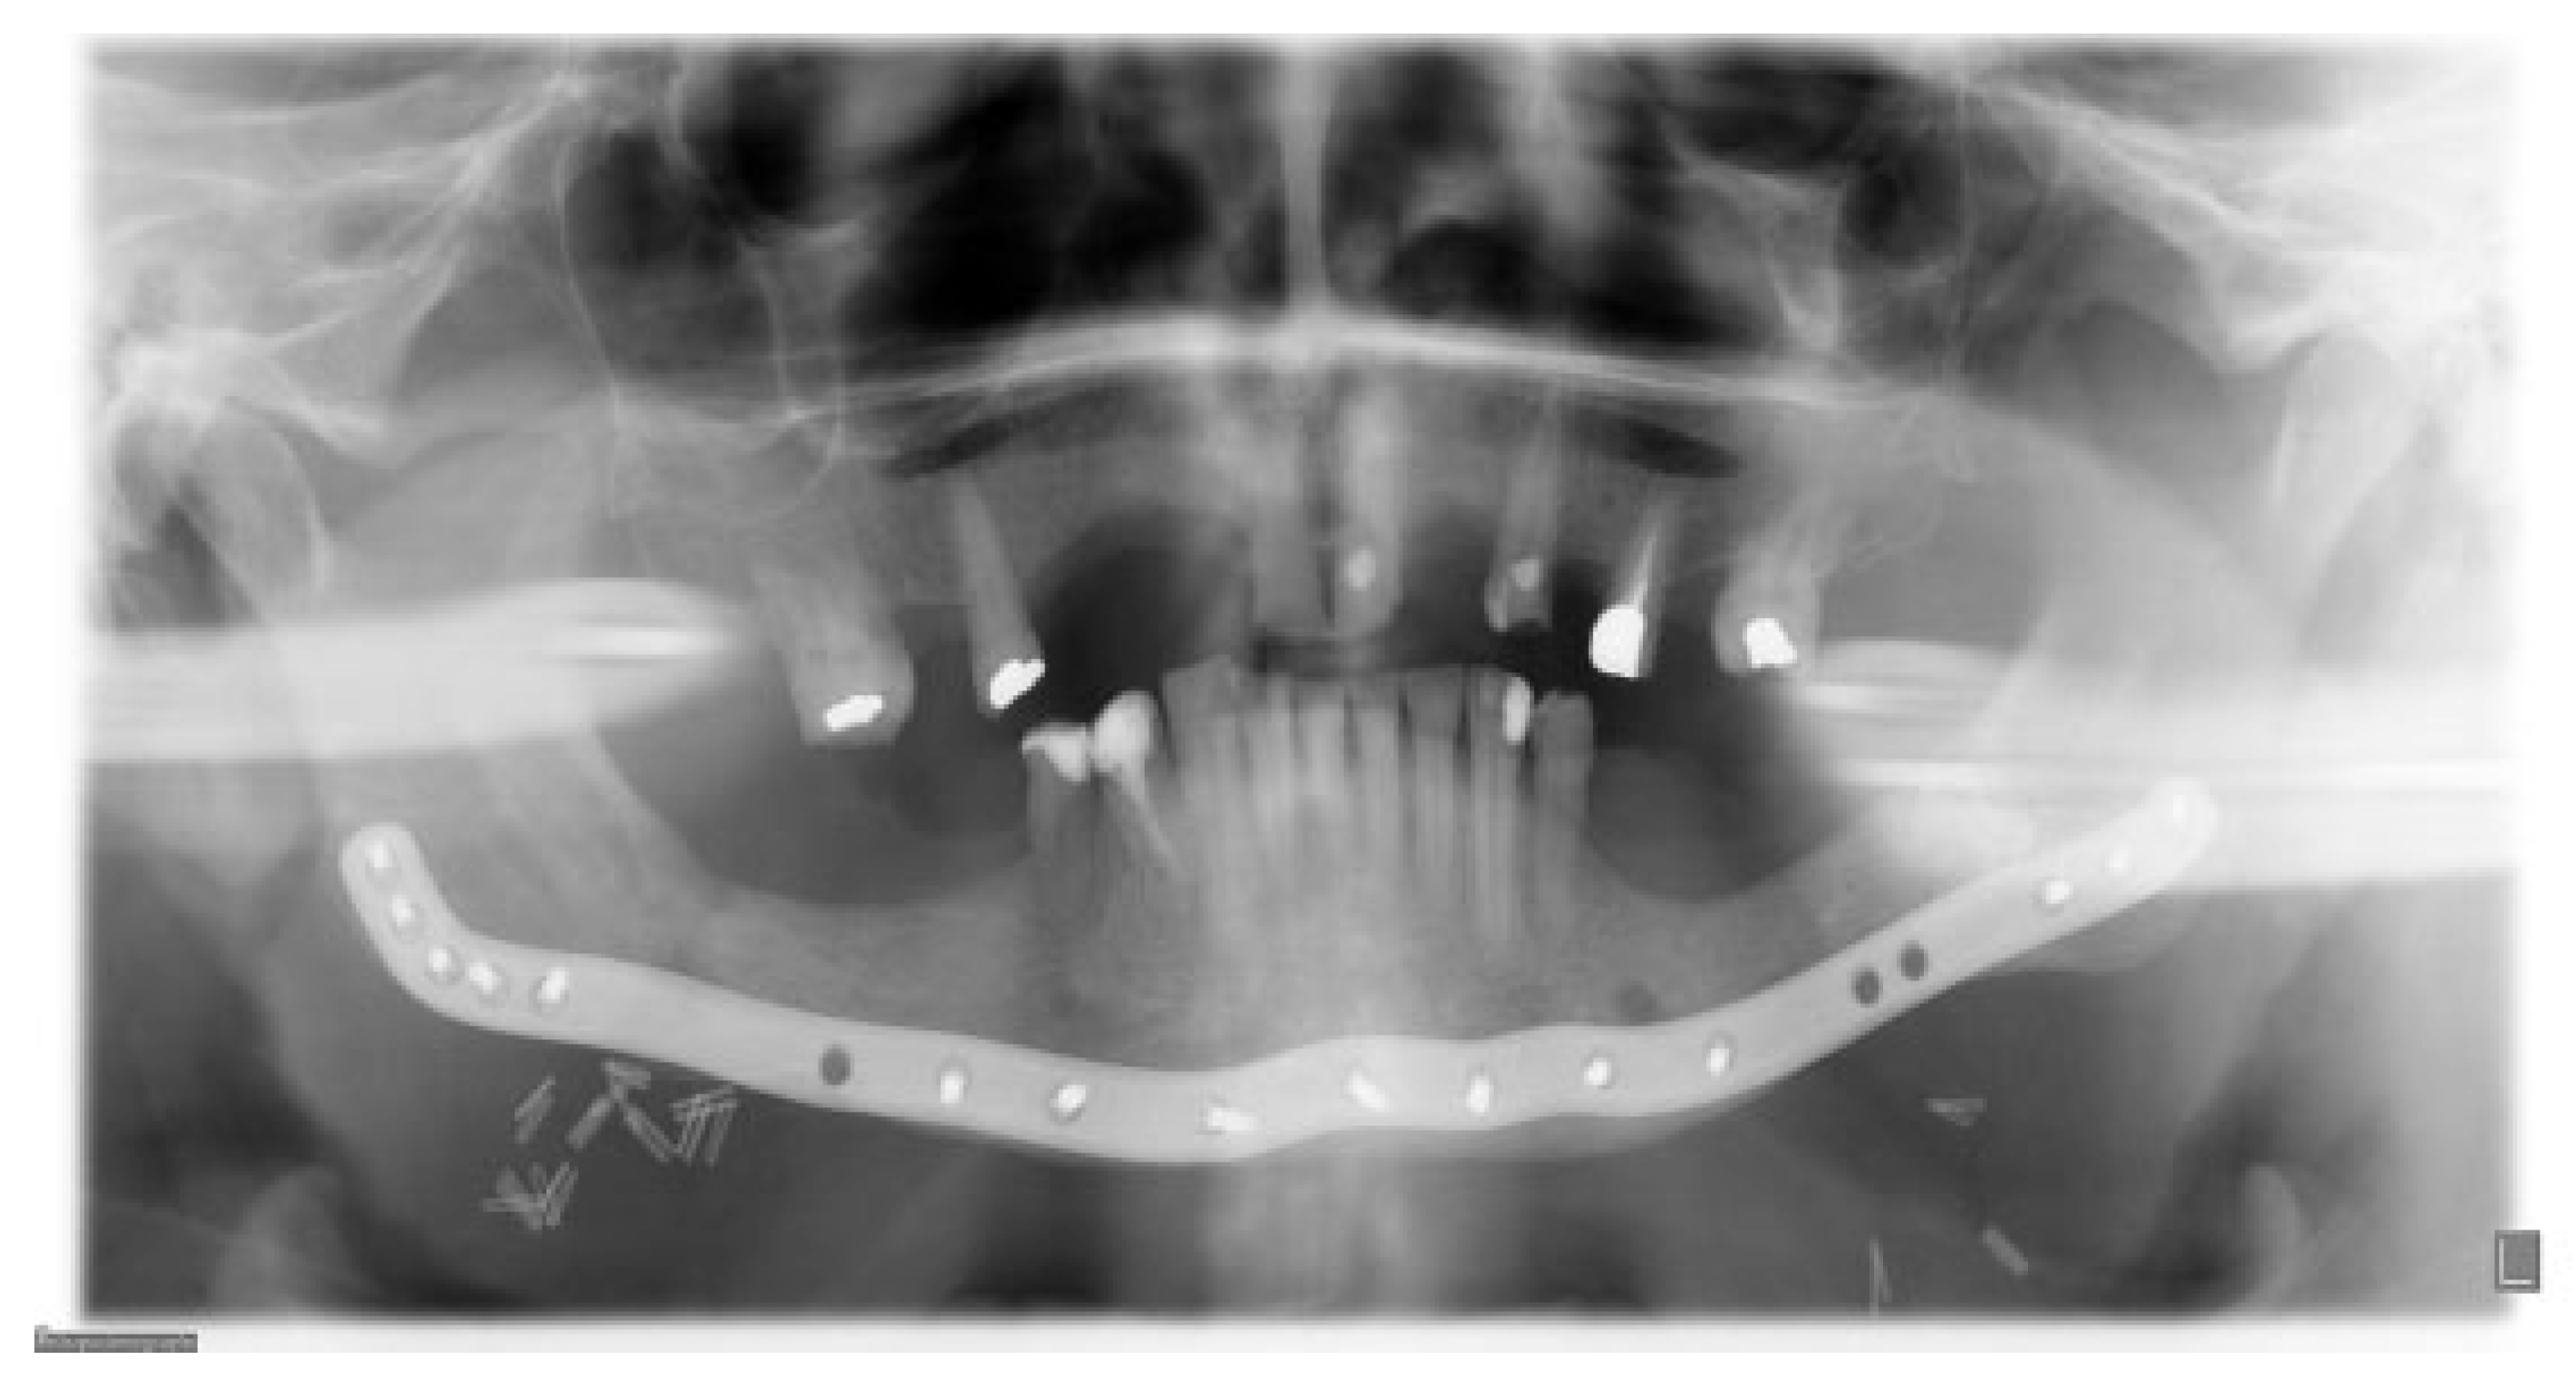

Figure 9.

The patient was placed in MMF during the procedure, enhancing the planned virtual rotations of segments in real life (posterior rotations of the proximal segments 4 degrees and anterior rotation of the distal segment of the mandible).

Figure 11.

Immediate postoperative situation captured with CBCT.

Figure 12.

Six months follow-up. Clinical and radiological healing is seen in the previous fracture areas in the region of the first molar on both sides of the mandible.